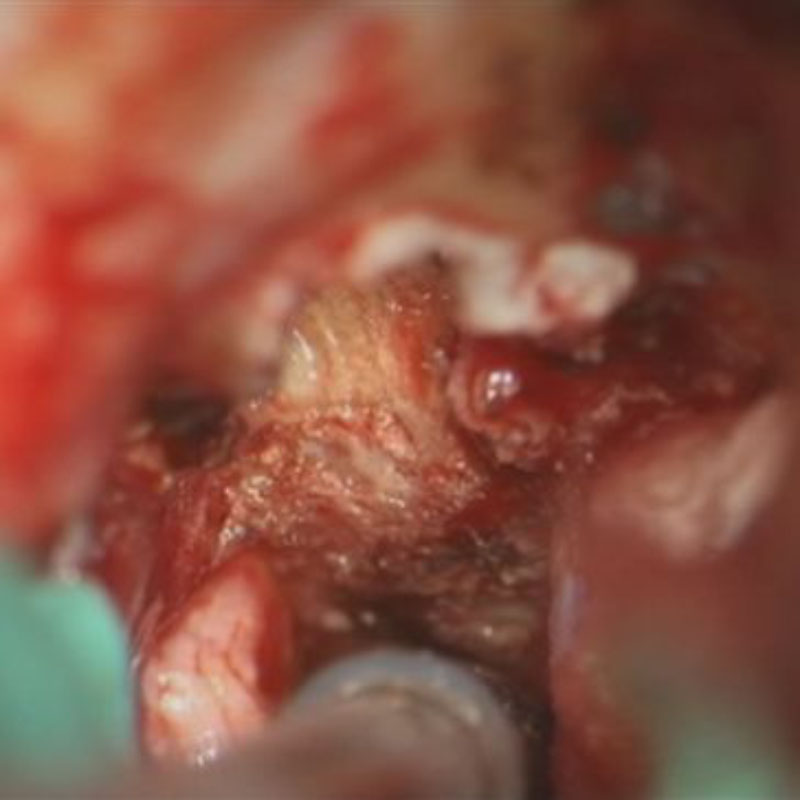

412

'23年5月

20代

小脳血管芽腫

頭蓋内腫瘍摘出術

No.’23_46 手術前1

No.’23_46 手術前2

No.’23_46 摘出 前

No.’23_46  摘出 中

No.’23_46 摘出 後